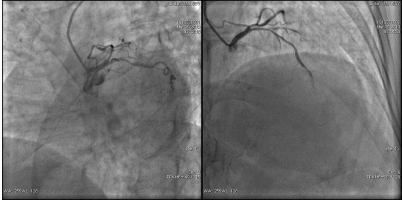

造影结果(一): LAD:中远段狭窄30%~40%,较长病变。LCX:中段狭窄80%~85%。

![]()

造影结果(二): RCA:近段狭窄85%~90%。

造影结论及应对策略: LAD:中远段狭窄30%~40%,较长病变。LCX:中段狭窄80%~85%。 RCA:近段狭窄约85%~90%。造影后向患者家属交代病情,与家属沟通后决定择期行介入治疗。